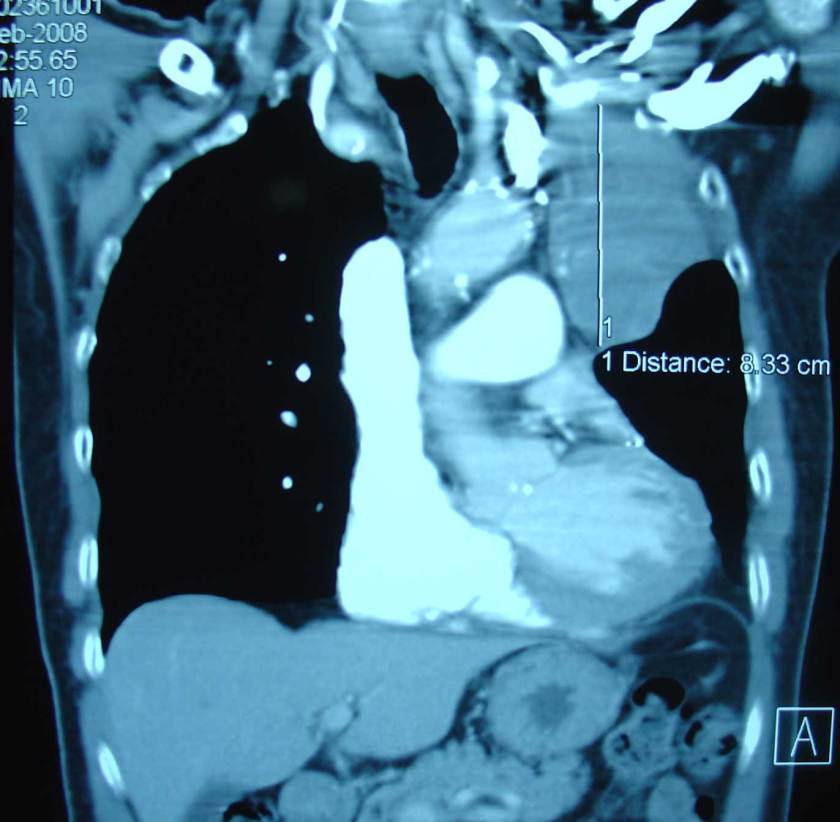

2. A CT scan was done and there was a big tumour in his lung. According to the doctor it was an aggressive tumour.

7. Since the tumour in the lung grew bigger, Tahe underwent twenty-eight times radiation treatments.

9. The result of the CT scan of the thorax and liver done on 21 February 2008 indicated:

• There is a small new left-sided pleural effusion.

• There is extensive volume loss demonstrated within the left hemithorax. This is secondary to left upper lobe collapse.

• There is mildly heterogenous pattern of enhancement to the collapse lung at the perihilar region.

• There is a possible recurrence of a left hilar pulmonary mass causing bronchial obstruction.

• There is a 8 mm pulmonary nodule in the right upper lobe.

• There is an enhancing mass adjacent to the falciform ligament.

• There is a 12 mm hepatic density within segment 6 of the liver.

• There are several subcentimetre hypodensities scattered throughout the liver which are too small to characterize.

• There is a left adrenal mass measuring 3.7 cm.

• There is a right adrenal mass measuring 2.7 cm.

• There is no destructive bony lesion identified.

It is obvious that the treatments thus far had failed to cure Tahe. The doctor suggested more chemotherapy. But Tahe declined further medical treatment. He and his family came to seek our help instead. Tahe was prescribed Capsule A & B, Liver Tea, Lung 1 & 2 Teas, LL-tea and Kidney Tea.